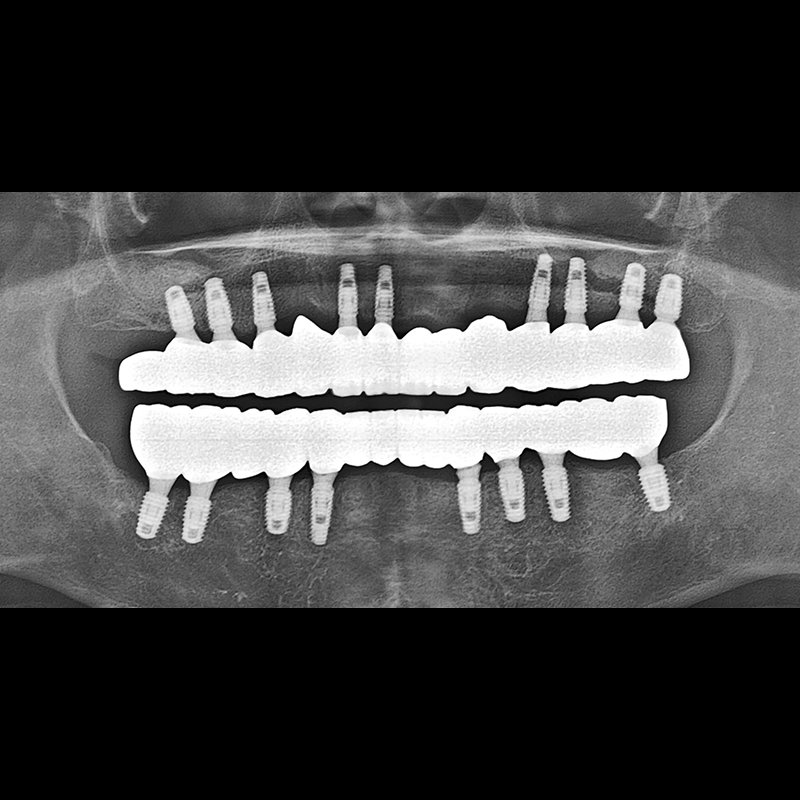

BEFORE AFTER

임플란트 전후사진 2025.05.30

결손된 치아 부분과 살리기 힘든 치아 위치에 임플란트를 식립하였습니다.